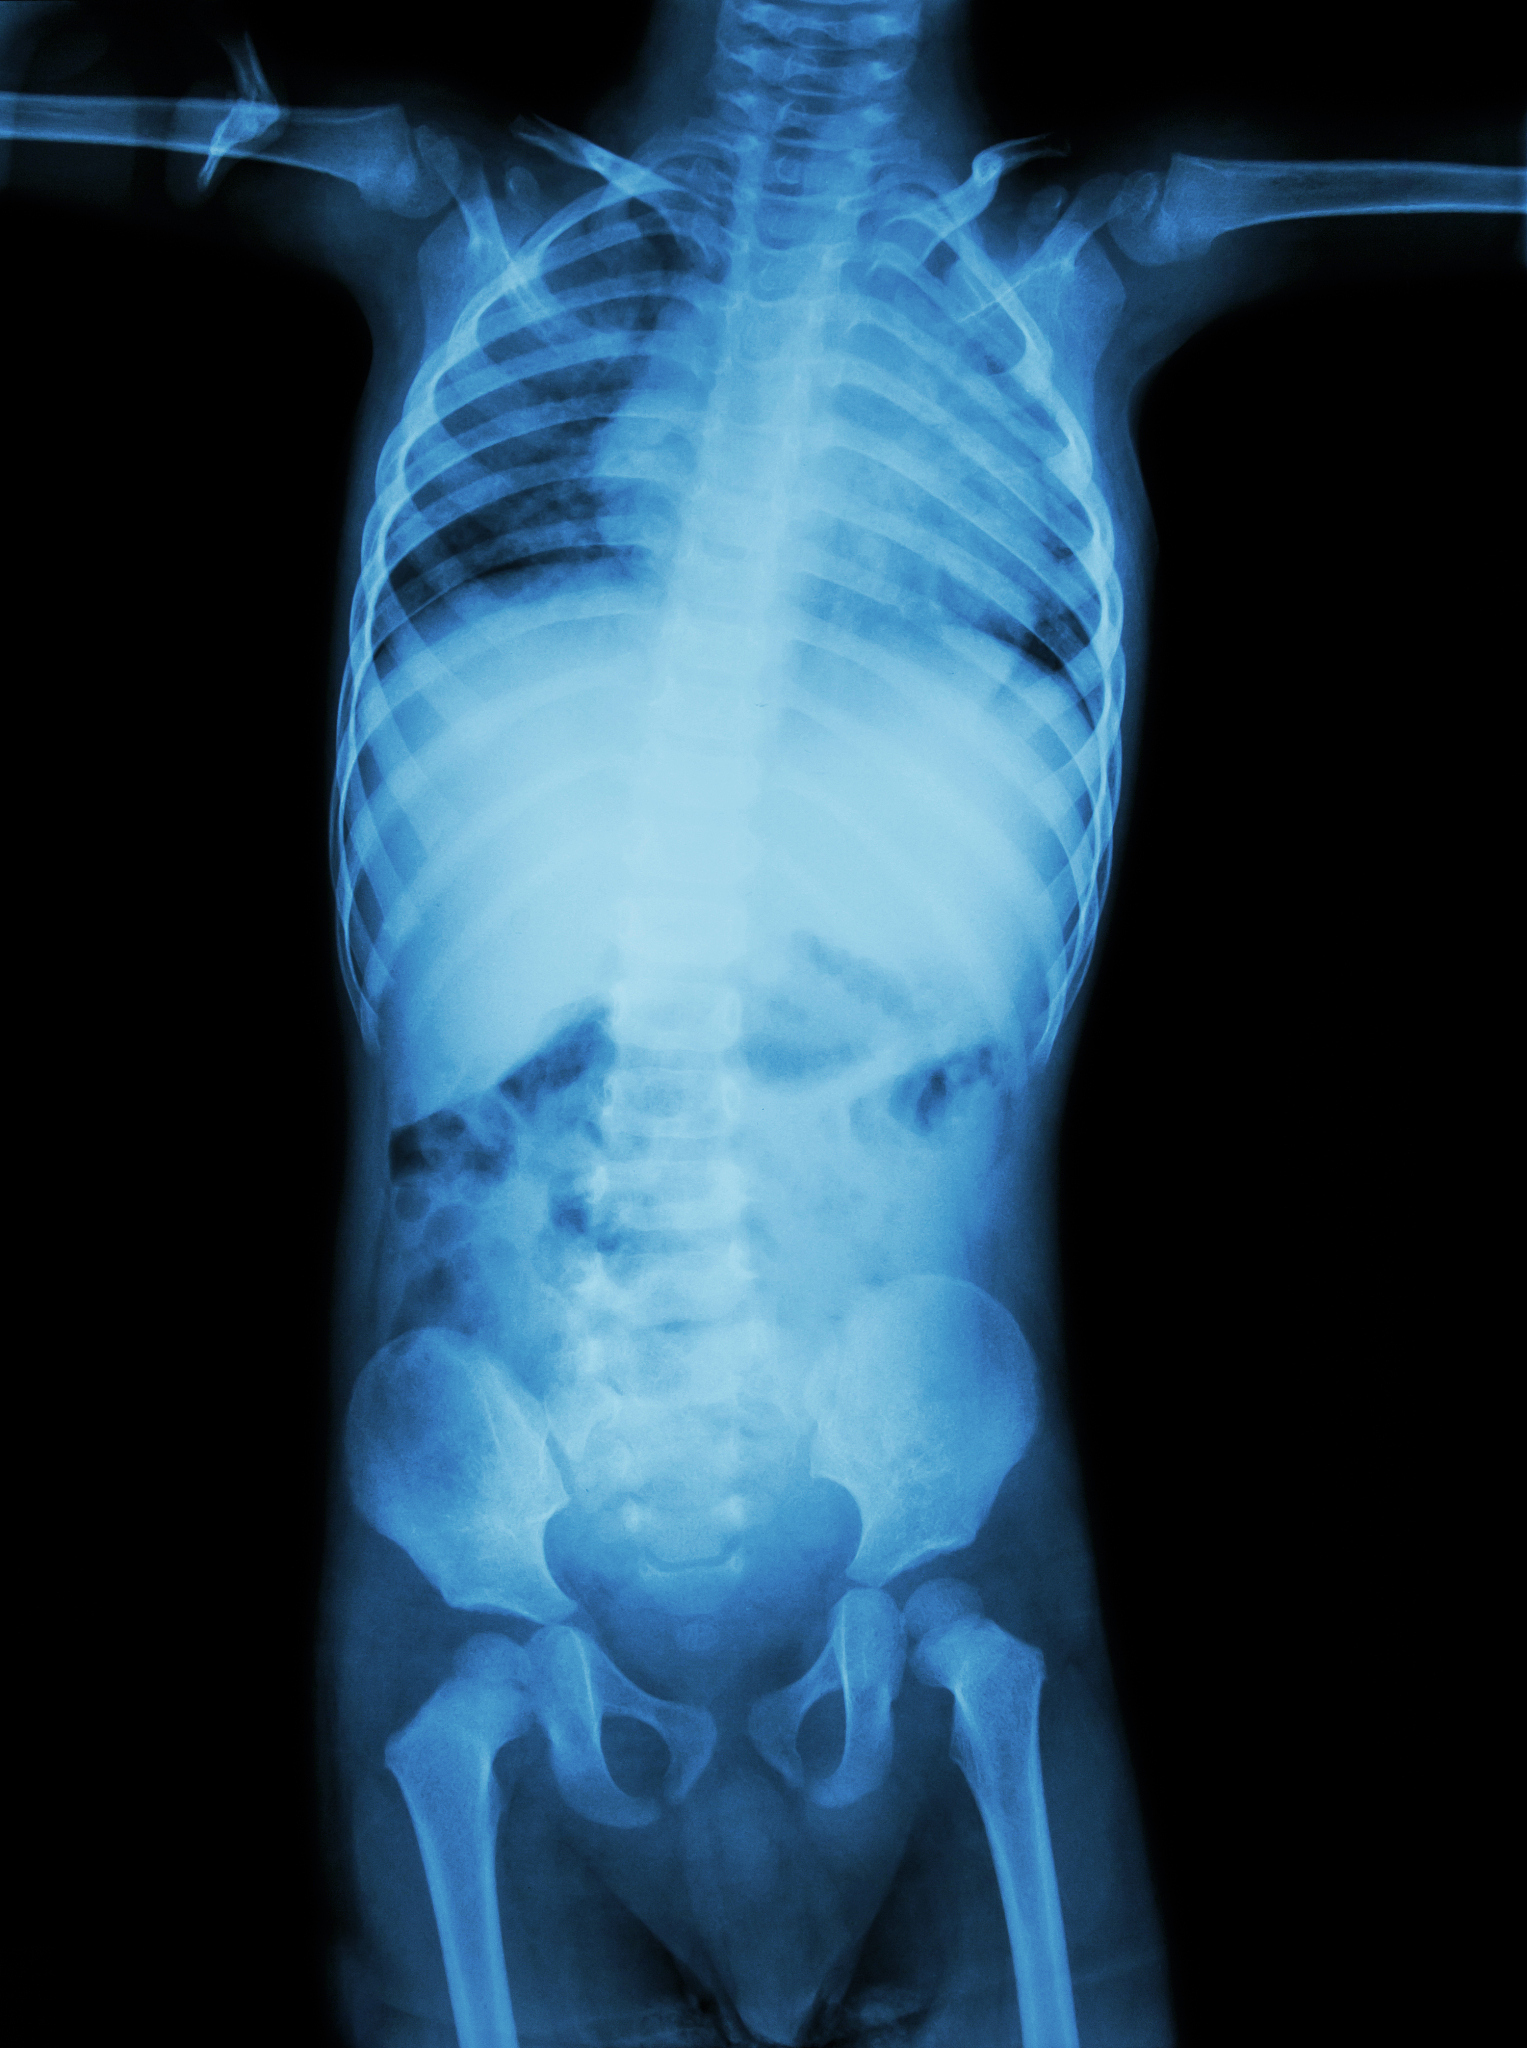

腹股沟疝气是一种常见疾病,指腹腔内脏器通过腹股沟区域的薄弱点或缺损突出到体表。本文将详细介绍腹股沟疝气的发病原因、典型症状、治疗方法以及预防措施,帮助您更好地了解和应对这一疾病。